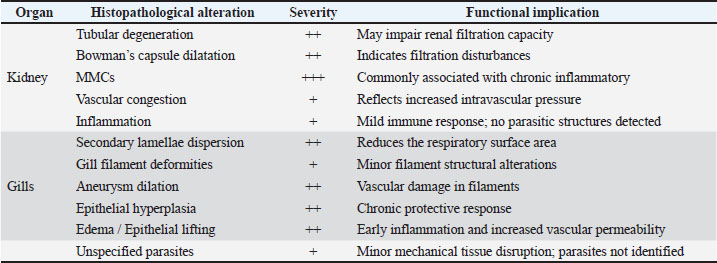

Fig. 13. Histopathology of the gills in an adult L. sceleratus showing congestion and telangiectasia of gill filament vessels (thick arrows) and lamellar dilation due to RBC accumulation (head arrows). ×40 H&E. Gill lesions were described separately for tissues with visible parasites and those without parasitic structures to improve interpretative clarity. Summary of lesionsHistopathological alterations in both kidney and gill tissues were classified using a semi-quantitative scoring system (+, ++, +++) (Fig. 14).

Fig. 14. Frequency distribution of lesion severity in the kidney and gills (+, ++, +++). Descriptive baseline data; no statistical comparisons due to lack of control. Kidney tissuesModerate tubular degeneration and Bowman’s capsule dilatation were recorded, whereas MMC proliferation was severe (+++). Vascular congestion and mild inflammation were observed. No parasitic structures were detected in kidney tissues. Observed alterations represent descriptive baseline histopathological changes. Gill tissuesModerate secondary lamellae dispersion, aneurysm dilation, epithelial hyperplasia, and edema/epithelial lifting were observed, whereas filament deformities and unidentified parasites were mild (+). Lesions were described separately for tissues with visible parasites and non-parasitized tissues to improve interpretative clarity. It should be noted that no unpolluted control group was included, and these observations represent descriptive baseline data; no causal inference regarding environmental stressors can be drawn (Table 1). Table 1. Semi-quantitative scoring of histopathological alterations in kidney and gill tissues of L. sceleratus along the Libyan coast (n=150 adult specimens).

DiscussionThe present study revealed pronounced histopathological alterations in both the kidneys and gills of L. sceleratus collected along the Libyan coast. Kidney lesions, including tubular degeneration, Bowman’s capsule dilatation, proliferation of MMCs, vascular congestion, and inflammatory infiltration, were associated with histologically detected structures, but no parasitic structures were detected in kidney tissues. These patterns are commonly reported in marine teleosts exposed to chronic environmental stressors (Ali et al., 2014; Steinel and Bolnick, 2017; Carreras-Colom et al., 2022). These lesions should be interpreted as descriptive indicators of physiological stress rather than direct evidence of chemical pollution or causality, consistent with Flores-Lopes and Thomaz (2011). Vascular abnormalities, including congestion and thickened vessel walls, were evident, which may reflect chronic circulatory disturbances or inflammatory responses rather than acute toxicity (Bernet et al., 1999; Thophon et al., 2003). Interstitial lymphohematopoietic tissue, inflammatory cell infiltration, and granulomatous formations suggest that parasitic or microbial challenges could contribute to renal lesions. Despite these histopathological changes, the sampled fish appeared healthy at capture, demonstrating the potential physiological resilience of marine teleosts. Fish kidneys possess compensatory mechanisms, and gills serve critical osmoregulatory and excretory functions, allowing survival despite structural alterations (Evans et al., 2005; Hwang et al., 2011; Hinton et al., 2018; Leone et al., 2018). Gradual development of renal lesions likely enables adaptation without acute organ failure. Gill tissues also exhibited pronounced alterations, including disorganization of secondary lamellae, club-shaped filament deformities, lamellar aneurysms, epithelial hyperplasia, and edema. These changes are consistent with chronic, sublethal tissue responses observed descriptively, without inferring specific environmental stressors or chemical toxicity (Sinha et al., 2014; Carvalho et al., 2020; Pramanik and Biswas, 2024). Unidentified parasitic structures, morphologically consistent with metazoan parasites, were observed based on histological appearance. Lesions were described separately for tissues with visible parasites and non-parasitized tissues to improve interpretative clarity (Sitjà-Bobadilla, 2008; Biller and Chagas, 2022). The proliferation of MMCs in gills reflects an immune response to tissue damage and cellular debris, reinforcing the descriptive nature of the findings. Vascular congestion and lamellar dilation due to RBC accumulation may indicate sublethal circulatory stress, but these observations are descriptive and not confirmed by physiological measurements (Triebskorn et al., 2007; Hasan et al., 2022). Moderate lesions (++), as summarized in Table 1 and illustrated in Fig. 14, were predominant, reflecting chronic, sublethal tissue responses rather than lethal injury. Overall, the kidney and gill lesions detected in L. sceleratus reflect chronic, sublethal tissue responses observed descriptively. No causal relationships with environmental stressors or chemical pollution can be inferred. Future studies incorporating water and sediment analyses, parasitological identification, and reference/control populations are recommended to strengthen the interpretation of these histopathological responses as potential biomarkers. LimitationsThis study is limited by the absence of environmental physicochemical data, the lack of a reference or control site, and the descriptive nature of the histopathological assessment. In addition, parasitic structures were not identified to species level, and quantitative prevalence metrics were not calculated. Accordingly, the findings should be interpreted as baseline descriptive observations rather than indicators of specific environmental stressors or pollution sources. ConclusionHistopathological examination of the kidneys and gills of L. sceleratus revealed tissue-level changes that serve as descriptive baseline data. Moderate to severe alterations were observed, including tubular degeneration, MMC proliferation, vascular congestion, secondary lamellae disorganization, and epithelial hyperplasia. No parasitic structures were detected in kidney tissues, while parasitic structures were observed only in some gill tissues and described separately. Despite these alterations, the species exhibits physiological compensation mechanisms, including renal adaptive responses and gill-mediated osmoregulation, supporting resilience under sublethal stress conditions. These findings are descriptive and should not be interpreted as direct evidence of environmental contamination or causation. All observations represent baseline histopathological data, intended to support future comparative and environmentally integrated studies rather than establish causal relationships. AcknowledgmentsThe authors sincerely thank the staff of the Pathology and Clinical Pathology Department (Faculty of Veterinary Medicine, Omar Al-Mukhtar University) and the Zoology Department (Faculty of Science, Omar Al-Mukhtar University) for their valuable support. Conflict of interestThe authors declare that there is no conflict of interest. FundingThis research received no specific grant. Authors' contributionsEda M. A. Alshailabi and Sana A. A. Mohammed contributed to the project idea and design, and Sana A. A. Mohammed and Ismail M. Hdud executed the study. Eda M. A. Alshailabi drafted and wrote the manuscript. Sana A. A. Mohammed and Samia M. Efkeren reviewed the manuscript critically. All authors have read and approved the final manuscript. Data availabilityAll data supporting the findings of this study are available within the manuscript. ReferencesAli, A.O., Hohn, C., Allen, P.J., Ford, L., Dail, M.B., Pruett, S. and Petrie-Hanson, L. 2014. The effects of oil exposure on peripheral blood leukocytes and splenic melano-macrophage centers of Gulf of Mexico fishes. Mar. Pollut. Bull. 79(1–2), 87–93; doi:10.1016/j.marpolbul.2013.12.036 Alshailabi, E., I.Al-Zail, N. and Abraheem, R. 2023. The effects of cigarette smoke on the epididymal tissues in adult male albino rats and the ameliorative effect of the Sidr honey. Libyan. J. Med. Res. 16(2 B), 79–92; doi:10.54361/LJMR.16.2B.08 Authman, M.M. 2015. Use of fish as bio-indicator of the effects of heavy metals pollution. J. Aquac. Res. Develop. 6, 328; doi:10.4172/2155-9546.1000328 Bernet, D., Schmidt, H., Meier, W., Burkhardt‐Holm, P. and Wahli, T. 1999. Histopathology in fish: proposal for a protocol to assess aquatic pollution. J. Fish Dis. 22(1), 25–34; doi:10.1046/j.1365-2761.1999.00134.x Biller, J.D. and Chagas, E.C. 2022. Mechanisms of resistance and tolerance against parasites in fish: the impairments caused by Neoechinorhynchus buttnerae in Colossoma macropomum. Anais. Da. Academia. Brasileira. De. Ciências. 94(4), e20210258; doi:10.1590/0001-3765202220210258 Carreras-Colom, E., Constenla, M., Dallarés, S. and Carrassón, M. 2022. Natural variability and potential use of melanomacrophage centres as indicators of pollution in fish species from the NW Mediterranean Sea. Mar. Pollut. Bull. 176, 113441; doi:10.1016/j.marpolbul.2022.113441 Carvalho, T.L.A.D.B., Do Nascimento, A.A., Gonçalves, C.F.D.S., Dos Santos, M.A.J. and Sales, A. 2020. Assessing the histological changes in fish gills as environmental bioindicators in Paraty and Sepetiba bays in Rio de Janeiro, Brazil. Latin. Am. J. Aquatic. Res. 48(4), 590–601. Christidis, G., Batziakas, S., Peristeraki, P., Tzanatos, E., Somarakis, S. and Tserpes, G. 2024. Another one bites the net: assessing the economic impacts of Lagocephalus sceleratus on small-scale fisheries in Greece. Fishes 9(3), 104; doi:10.3390/fishes9030104 Evans, D.H., Piermarini, P.M. and Choe, K.P. 2005. The multifunctional fish gill: dominant site of gas exchange, osmoregulation, acid-base regulation, and excretion of nitrogenous waste. Physiological Rev. 85(1), 97–177; doi:10.1152/physrev.00050.2003 Flores-Lopes, F. and Thomaz, A. 2011. Histopathologic alterations observed in fish gills as a tool in environmental monitoring. Braz. J. Biol. 71(1), 179–188; doi:10.1590/s1519-69842011000100026 Hasan, J., Ferdous, S.R., Rabiya, S.B.A., Hossain, M.F., Hasan, A.M. and Shahjahan, M. 2022. Histopathological responses and recovery in gills and liver of Nile tilapia (Oreochromis niloticus) exposed to diesel oil. Toxicol. Rep. 9, 1863–1868; doi:10.1016/j.toxrep.2022.10.005 Hinton, D.E., Baumann, P.C., Gardner, G.R., Hawkins, W.E., Hendricks, J.D., Murchelano, R.A. and Okihiro, M.S. 2018. Histopathologic biomarkers. In Biomarkers: biochemical, physiological, and histological markers of anthropogenic stress. Eds., Huggett, R.A. Kimerle, P.M. Mehrle, Jr.,Bergman, H. Chelsea, MI: CRC Press, pp: 155–209; doi: 10.1201/9781351070270. Hose, J.E., Mcgurk, M.D., Marty, G.D., Hinton, D.E., Brown, E.D. and Baker, T.T. 1996. Sublethal effects of the Exxon Valdez oil spill on herring embryos and larvae: morphological, cytogenetic, and histopathological assessments, 1989–1991. Can. J. Fisheries Aquatic Sci. 53, 2355–2365. Hwang, P.P., Lee, T.H. and Lin, L.Y. 2011. Ion regulation in fish gills: recent progress in the cellular and molecular mechanisms. Am. J. Physiol–Regulatory. Integr. Comparative. Physiol. 301, R28–R47; doi:10.1152/ajpregu.00047.2011 Katikou, P., Gokbulut, C., Kosker, A.R., Campàs, M. and Ozogul, F. 2022. An updated review of tetrodotoxin and its peculiarities. Mar. Drugs 20(1), 47; doi:10.3390/md20010047 Leone, O., Valdecantos, S. and Martínez, V. 2018. Histopathological markers of environmental stress in the fish Odonthestes bonariensis (Atheriniformes, Atherinopsidae) in two reservoirs of Argentina. UNED Res. J. 10(2), 273–282; doi: 10.22458/urj.v10i2.1909 Mohmmed, S., Ekhnefer, A., Fadel, A. and Sharif, M. 2023. Prevalence of some parasitic infestations in Lagocephalus sceleratus in Eastern Libya. AlQalam J. Med. Appl. Sci. 6(2), 608–616. Moshaie-Nezhad, P., Bahari, Z., Jangravi, Z., Zarei, S.M. and Iman, M. 2021. The effect of Descurainia sophia seed extract on nephrotoxicity markers induced by acetaminophen in mice. J. Adv. Med. Biomed. Res. 29(134), 139–144; doi:10.30699/jambs.29.134.139 Osman, A.G.M. 2010. Enzymatic and histopathologic biomarkers as indicators of aquatic pollution in fishes. Natural. Sci. 2(11), 1302–1311; doi:10.4236/ns.2010.211158 Paul, M. and Chanda, M. 2017. Histological slide preparation of fish tissues (paraffin method). Asutosh College Kolkata India 1, 1–5; doi: 10.13140/RG.2.2.15130.34243 Pinna, M., Zangaro, F., Saccomanno, B., Scalone, C., Bozzeda, F., Fanini, L. and Specchia, V. 2023. An overview of ecological indicators of fish to evaluate the anthropogenic pressures in aquatic ecosystems: from traditional to innovative DNA-based approaches. Water 15(5), 949; doi:10.3390/w15050949 Pramanik, S. and Biswas, J.K. 2024. Histopathological fingerprints and biochemical changes as multi-stress biomarkers in fish confronting concurrent pollution and parasitization. iScience 27(12), 111432; doi:10.1016/j.isci.2024.111432 Shahid, S., Sultana, T., Sultana, S., Hussain, B., Al-Ghanim, K.A., Al-Bashir, F., Riaz, M.N. and Mahboob, S. 2022. Detecting aquatic pollution using histological investigations of the gills, liver, kidney, and muscles of Oreochromis niloticus. Toxics 10(10), 564; doi:10.3390/toxics10100564 Shakman, E., Eteayb, K., Taboni, I. and Ben Abdalha, A. 2019. Status of marine alien species along the Libyan coast. J. Black Sea / Medit. Environ. 25(2), 188–209. Sinha, A.K., Matey, V., Giblen, T., Blust, R. and De Boeck, G. 2014. Gill remodeling in three freshwater teleosts in response to high environmental ammonia. Aquatic Toxicol. 155, 166–180; doi:10.1016/j.aquatox.2014.05.016 Sitjà-Bobadilla, A. 2008. Living off a fish: a trade-off between parasites and the immune system. Fish Shellfish Immunol. 25(4), 358–372; doi:10.1016/j.fsi.2008.03.018 Steinel, N.C. and Bolnick, D.I. 2017. Melanomacrophage centers as a histological indicator of immune function in fish and other poikilotherms. Front. Immunol. 8, 827; doi:10.3389/fimmu.2017.00827 Thophon, S., Kruatrachue, M., Upatham, E.S., Pokethitiyook, P., Sahaphong, S. and Jaritkhuan, S. 2003. Histopathological alterations of white seabass (Lates calcarifer) in acute and subchronic cadmium exposure. Environ. Pollut. 121(3), 307–320; doi:10.1016/S0269-7491(02)00270-1 Triebskorn, R., Casper, H., Scheil, V. and Schwaiger, J. 2007. Ultrastructural effects of pharmaceuticals (carbamazepine, clofibric acid, metoprolol, diclofenac) in rainbow trout (Oncorhynchus mykiss) and common carp (Cyprinus carpio). Anal. BioAnal. Chem. 387(4), 1405–1416; doi:10.1007/s00216-006-1033-x Ulman, A., Yildiz, T., Demirel, N., Canak, O., Yemişken, E. and Pauly, D. 2021. The biology and ecology of the invasive silver-cheeked toadfish (Lagocephalus sceleratus), with emphasis on the Eastern Mediterranean. NeoBiota 68, 145–175; doi:10.3897/neobiota.68.71767 Wahidi, B.R., Hakimah, N., Suhermanto, A., Triyastuti, M.S. and Utami, D.A.S. 2025. Histopathological analysis of gills, liver, and kidneys of Nile tilapia (Oreochromis niloticus) affected by feverish Lapindo mud in Porong River, Sidoarjo-East Java. J. Aquac. Fish. Health. 14(1), 114–121; doi:10.20473/jafh.v14i1.61592 | ||